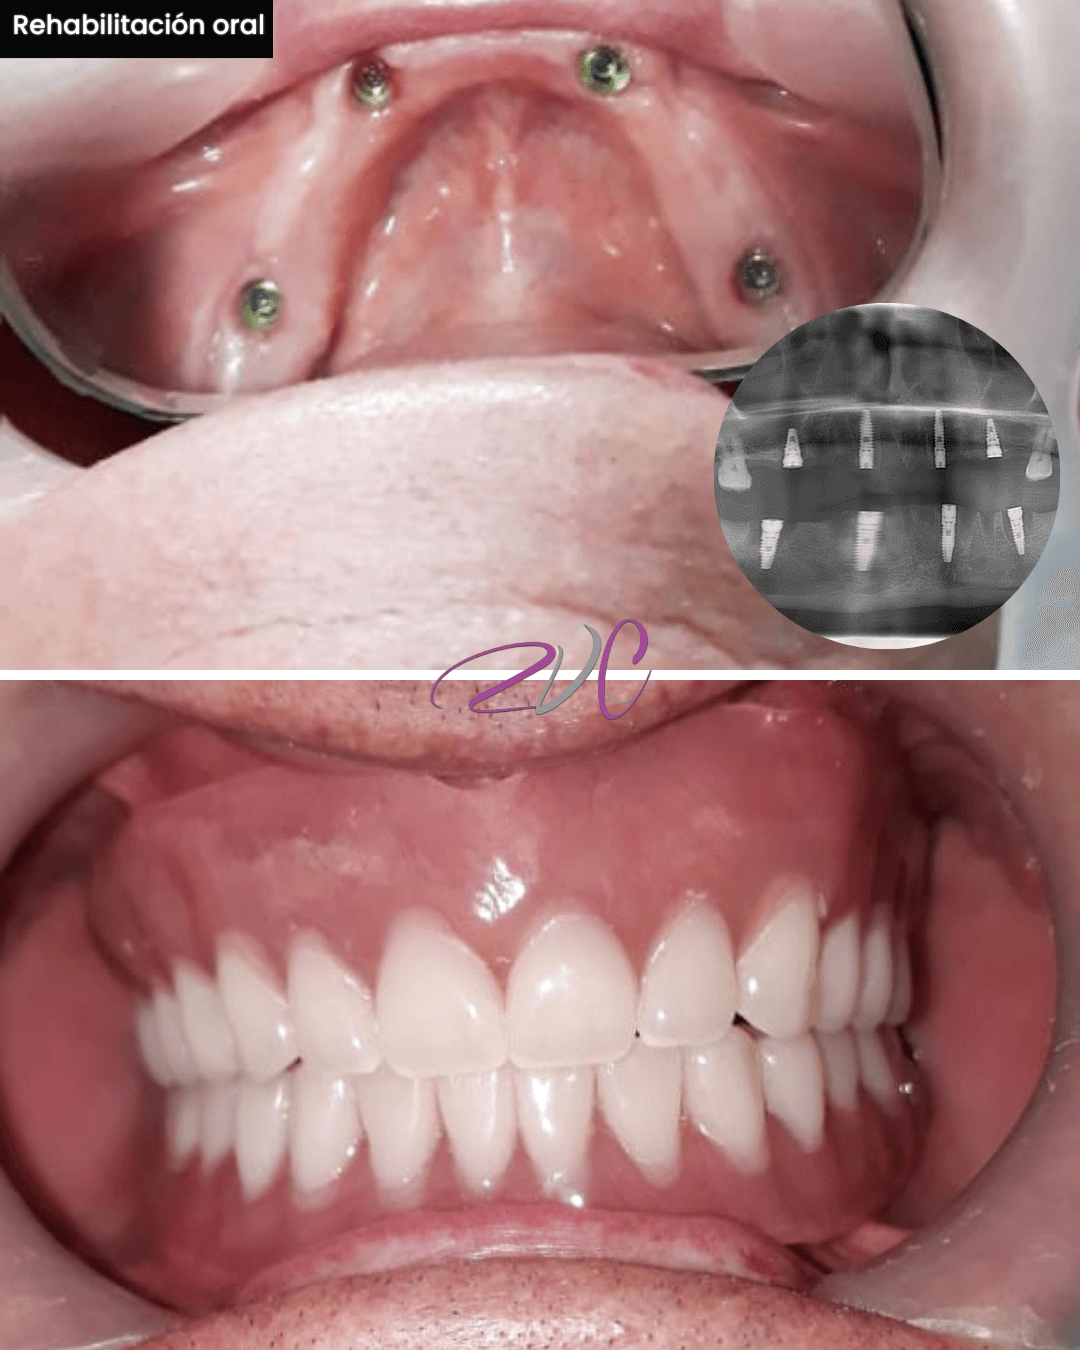

Rehabilitación Oral

Especialidad enfocada en restaurar la funcionalidad y estética de la boca cuando se han perdido dientes o estructuras dentales. Incluye tratamientos como coronas, puentes, prótesis fijas o removibles e implantes dentales. Ideal para devolver salud, estabilidad y confianza al paciente.